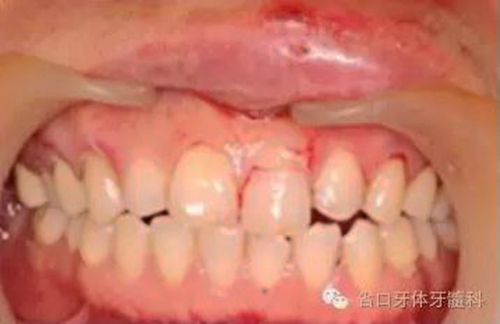

圖2. 術(shù)前口內(nèi)照片,21/冠折。

圖3. 術(shù)前X線片